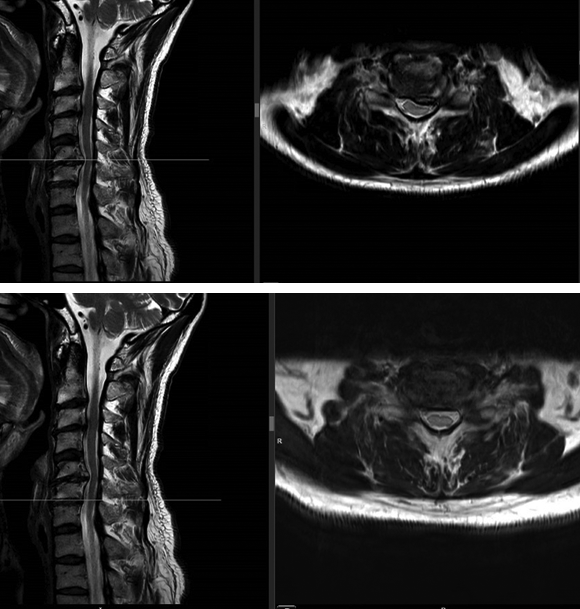

A magnetic resonance imaging demonstrated a cervical spinal stenosis with cord compression C5-6 L, foraminal stenosis C5-6 L, and C6-7 bilateral (Fig 5).

A computed tomographic scan showed large posterior osteophytes C5-6 and spondylosis anterior (Fig 6).